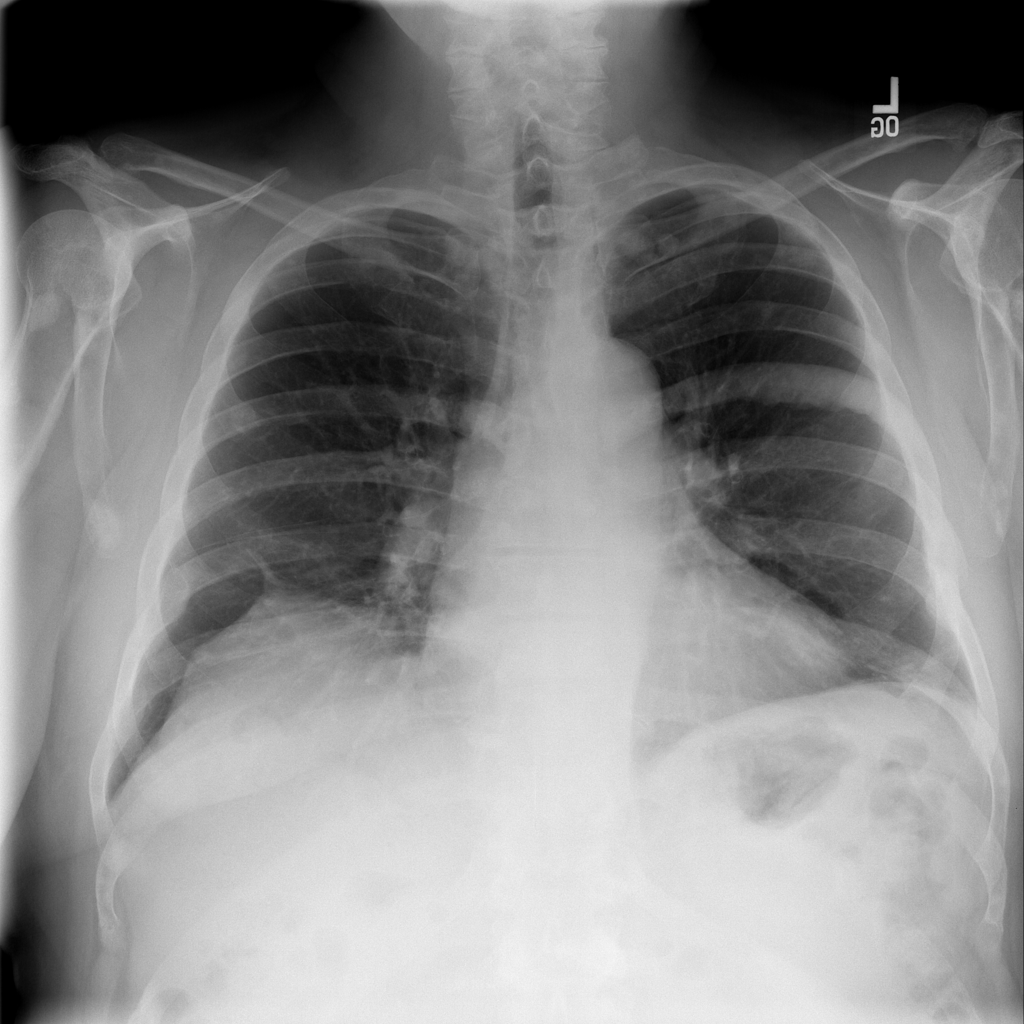

Showing up to 90 reference images for Hernia.

PAT-C048 · IMG-000Hernia

PAT-C048 · IMG-000

PA